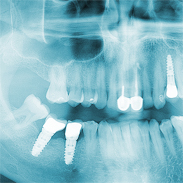

Die jeweilige Entscheidung für die ein oder andere Vorgehensweise hängt vom individuellen Zahnstatus des Patienten ab.

Durch die Entwicklung neuer Werkstoffe und Techniken hat die Implantologie ein sehr hohes Niveau mit hervor-

ragenden Möglichkeiten für den Patienten erreicht.

Da wir in unserem Labor seit vielen Jahren alle gängigen Implantatsysteme verarbeiten, verfügen wir über eine große Erfahrung auf diesem Gebiet der Zahntechnik und stehen Ihnen als kompetenter Ansprechpartner gerne zur Verfügung.